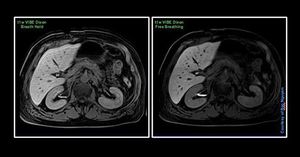

MRI Liver Imaging with Primovist – Hepatobiliary phase @ Siemens 1.5T Aera Hepatobiliary phase on a normal function liver would be at approx. 20min-120min. You have good time to acquire that phase with great optimized sequences. This patient was not a good breath holder, was tired at the end of the exam. So modifying this t1w VIBE Dixon to a free breathing approach, gave the results as seen. The scan time of this breath hold vibe was around 15sec, and the free breathing was 1min and 30sec. Nevertheless, longer scan time on the free breather, but the results speaks for itself.#Siemens_MRI #siemens #mri #abdominal_liver #primovist #bayer #gadolinium